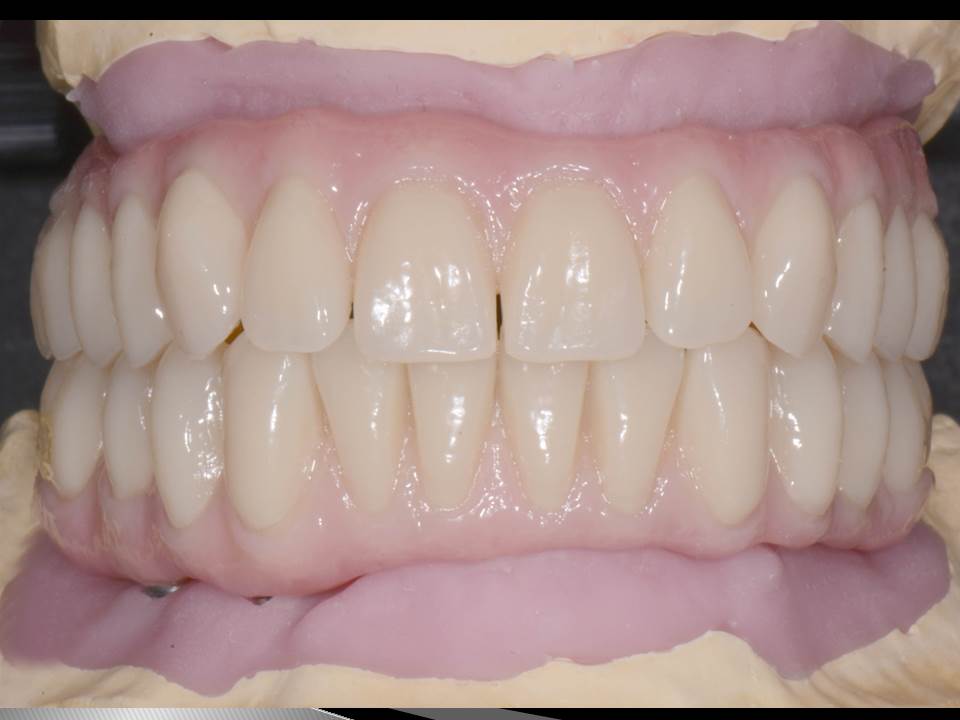

Prótesis fija OT BRIDGE

E - BOOK y CASOS CLÍNICOS

CASOS CLÍNICOS